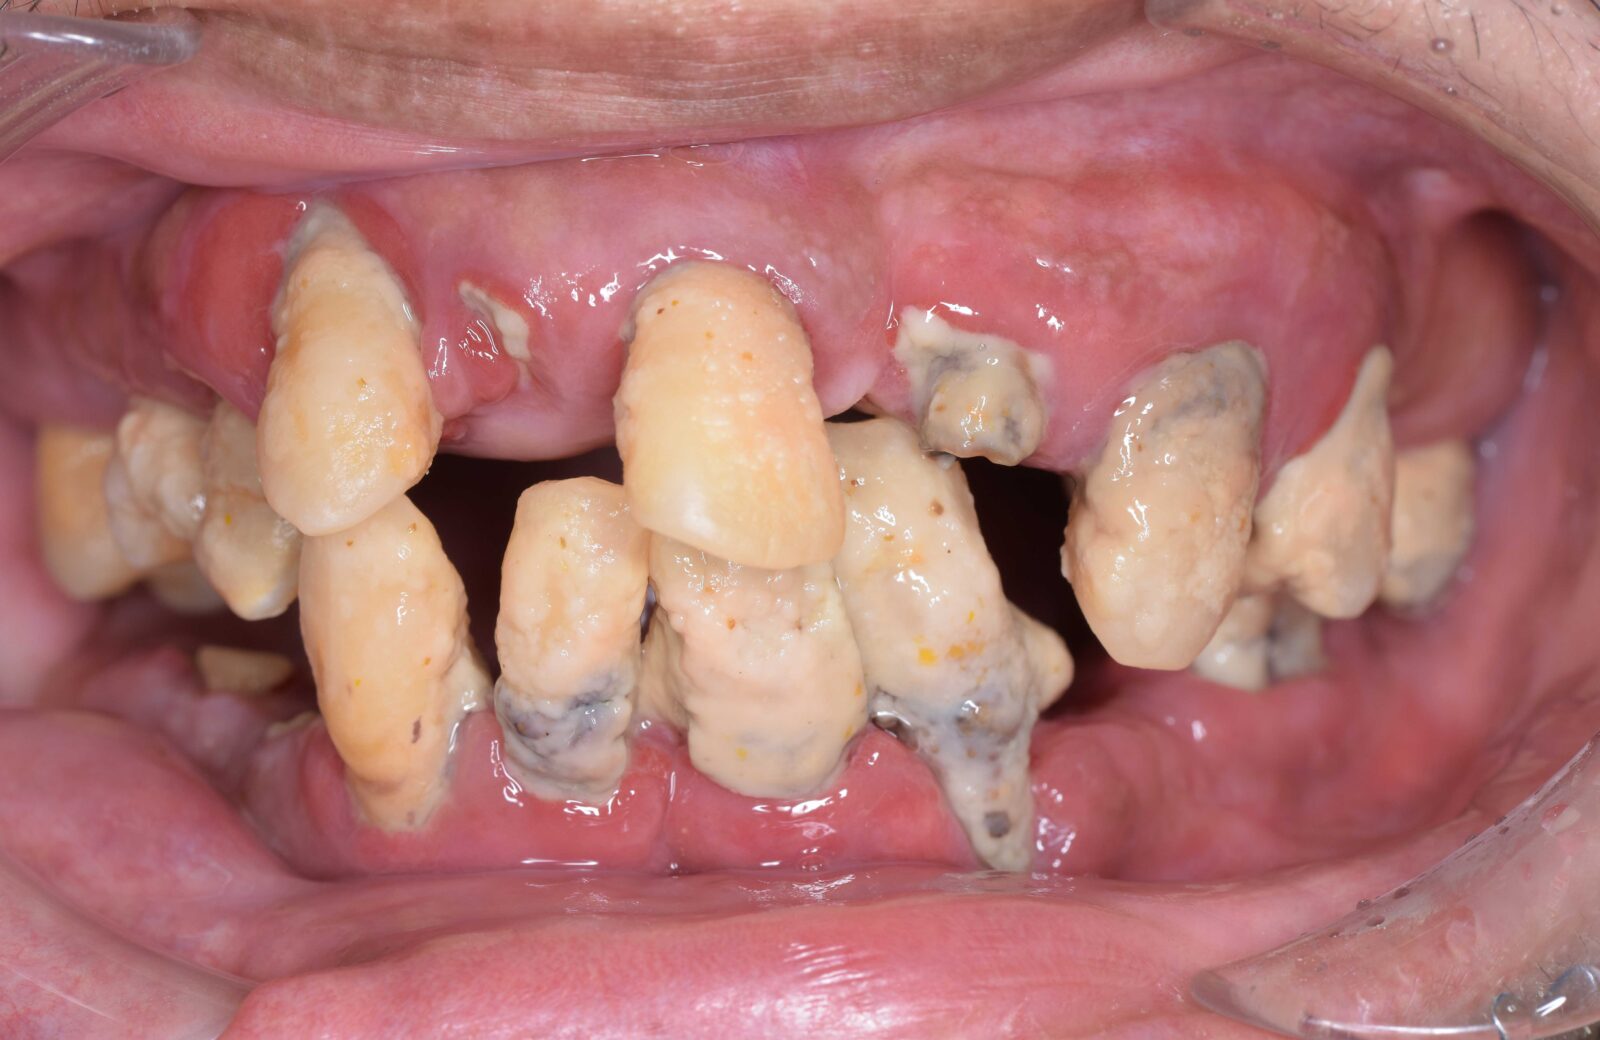

• 治療前

• 治療後

ボロボロの歯を「総合歯科治療」で ※保険外※

ボロボロの状態の治療は「包括的かつ総合的な治療」が必要となります。そのため当院では保険外で治療を行います。

多くの方が、重度のむし歯や歯周病で、抜けてしまっている歯もあるため、まずは虫歯や歯周病治療を行い、残せる歯はしっかり残したうえで、欠損部分の治療を行います。欠損部分に関しては、インプラント、ブリッジ、入れ歯、ケースによってはオールオン4という治療の中から治療法を決定します。